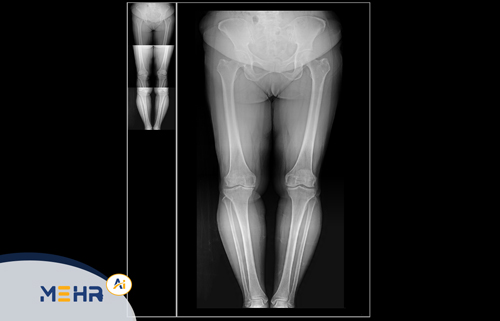

Web DICOM یک سامانه تحت‌وب برای مشاهده و مدیریت تصاویر پزشکی با فرمت DICOM است.

این سیستم به‌صورت مستقیم به سرور PACS متصل شده و امکان دسترسی بلادرنگ (Real-Time Access) به تصاویر را از طریق اینترنت فراهم می‌سازد.

• مشاهده فوری تصاویر CT، MRI، سونوگرافی و ماموگرافی از طریق مرورگر

• مشاهده تصاویر پزشکی در مراکز رادیولوژی و تصویربرداری

• دسترسی آنلاین پزشکان متخصص برای بررسی و تفسیر تصاویر

• استفاده بیماران جهت مشاهده نتایج و دریافت نسخه دیجیتال تصاویر خود